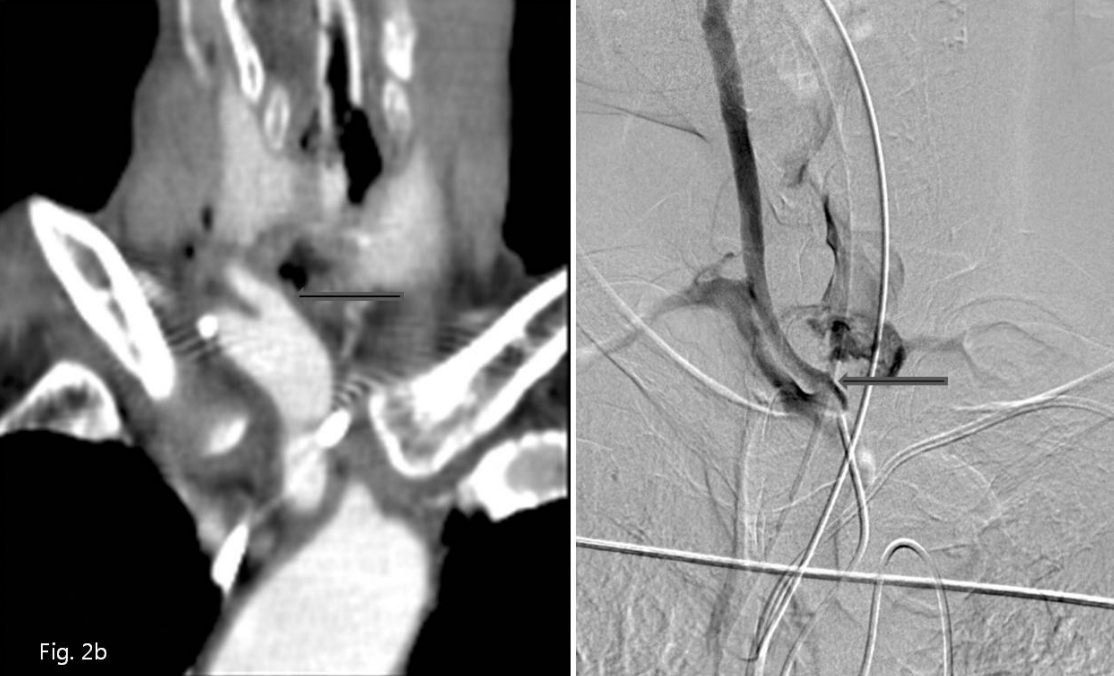

A. Contrast enhanced axial CT scans show suspicious focal fistula from the upper medial wall of right proximal common carotid artery to the tracheostomy lumen (arrow).

B. Coronal reformatted CT image right innominate ar teriography show focal bulging of the upper medial wall of right proximal common carotid artery and contrast leakage into tracheostomy site (arrows).

Fig. 4

After selection of fistula itself near the mesh of plug device with a microcatheter, microcoils wer e inserted into the fistula itself and well fixed on completion angiography.